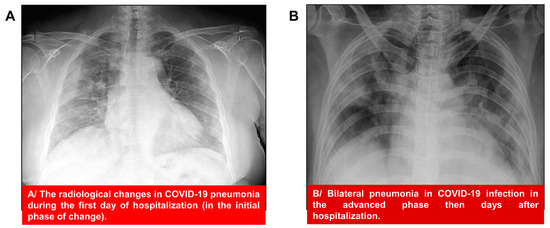

2.3. Chest X-ray in a Patient with COVID-19

4.5. Radiography of the Lungs